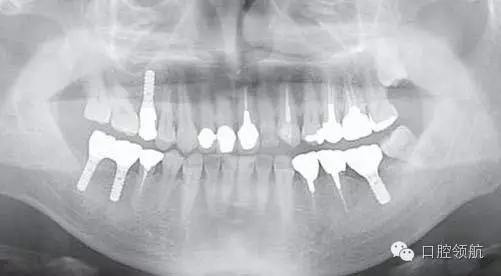

患者,38歲,男性,作為需要全面治療的患者來院?;局委熀螅蚁骂M磨牙區(qū)及右上頜磨牙區(qū),還有拔牙后的左下頜磨牙缺損區(qū),擬進行種植修復(fù)。圖1為初診時的曲面斷層影像,問診,模型診斷,曲面斷層檢查均未見異常,因此,最先在右下頜磨牙缺損區(qū),繼而在右上頜磨牙缺損區(qū)植入種植體,這些種植體愈合良好。

圖1 初診時的曲面斷層影像。

對患者進行詳細說明后,拔除后等待骨愈合6個月,再度植入手術(shù)。第二次植入時,注意了沖水充分,根據(jù)骨的狀態(tài),在缺損部中央植入。植入后2個月,按常規(guī)戴入上部結(jié)構(gòu),約6個月后,曲面斷層影像和口內(nèi)均未見異常,愈合良好(圖9)。

圖9 再植入后6個月的曲面斷層影像。